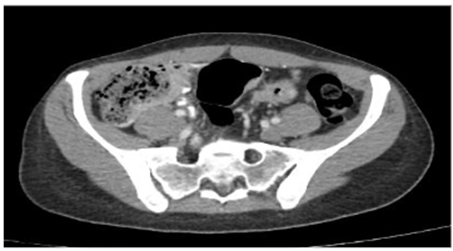

Se decidió realizar una tomografía de abdomen (figura 3) que mostró engrosamiento concéntrico de las paredes del colon sigmoide de 7 mm de espesor, de aspecto inespecífico, de probable etiología inflamatoria, asociado a coprostasis en el colon ascendente y transverso, sin observarse adenomegalias, y endoscopia de vías digestivas altas, cuyo único hallazgo fue gastritis crónica. En la radiografía de tórax de control (figura 4) se aprecian cambios dados por opacidades reticulares bilaterales en 4 cuadrantes y aumento del proceso reticular previo, por lo que se hace necesario la toma de biopsia pulmonar por parte de cirugía de tórax.